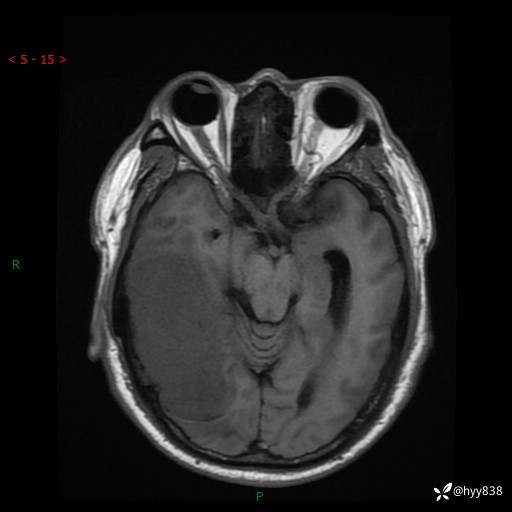

患者性别:男

患者年龄:56岁

简要病史:外院CT提示脑膜瘤,为进一步诊治来我院

辅助检查:MRI

临床诊断:颅脑占位

颅脑MRI平扫+增强